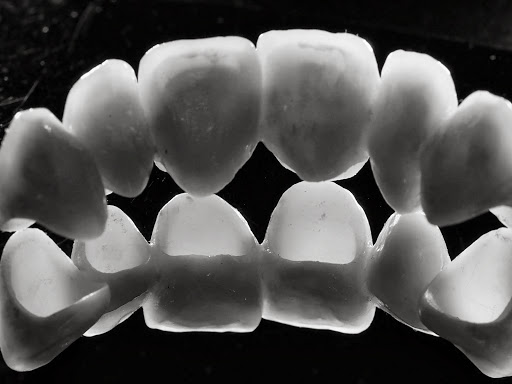

Keine Metalle im Mund